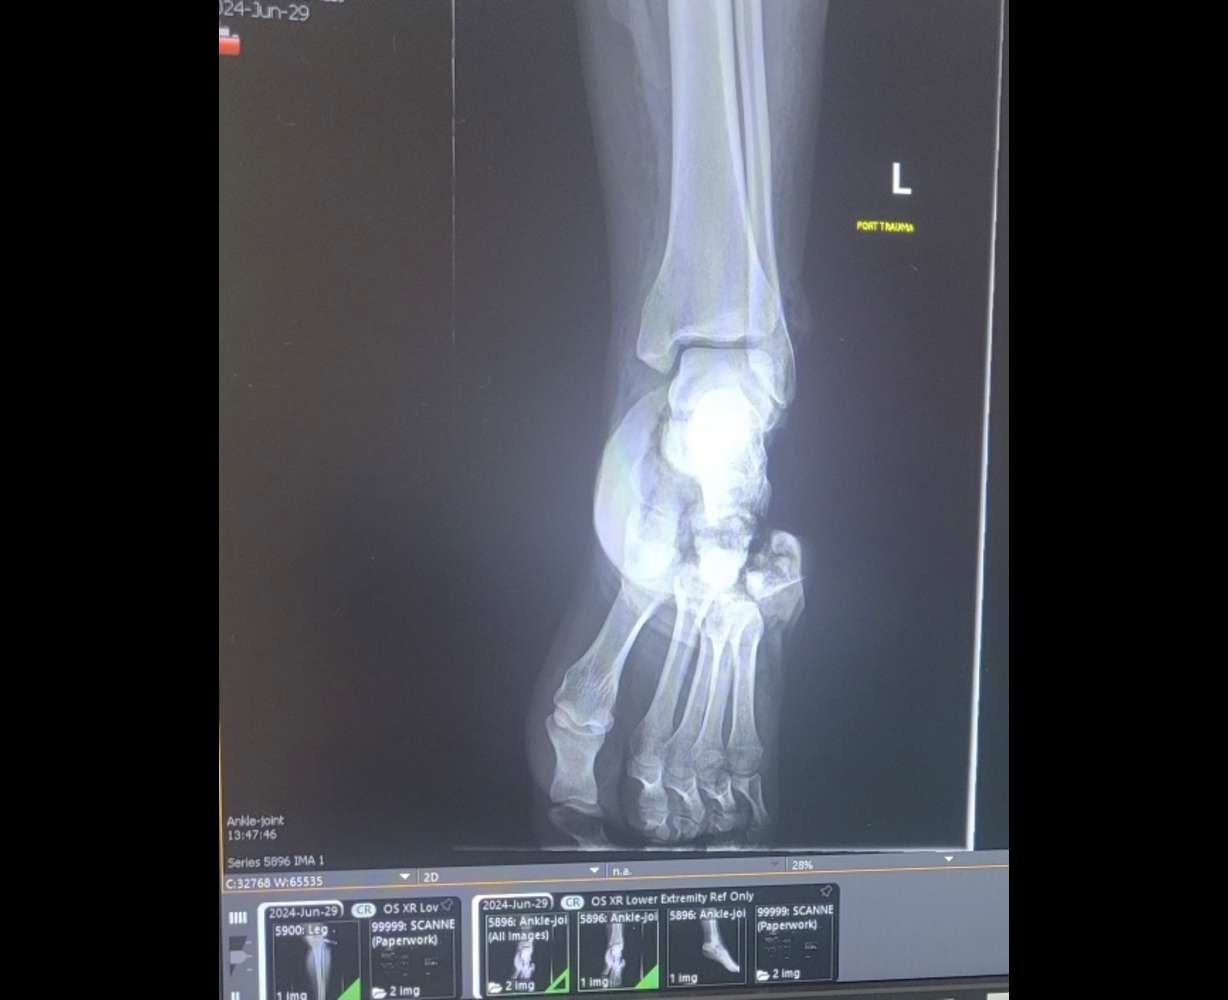

"She just started yelling from behind, 'Dad, my foot, my foot!' I was able to look down and see it behind me," Matt Anderson said. "Half her foot was gone, and the back of the bike was twisted in half."

"She had a partially amputated foot," she said. "The first thing I found was a scarf on a lady that had also stopped — I used that as a tourniquet until the police officer got there."

Doctors said Aspen Anderson will have a long road to recovery and might not have full use of her foot for some time, but she is still in good spirits.

"She could have balance issues later," Aspen's mother added.